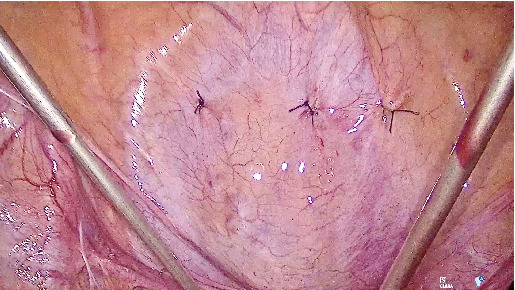

Tension-free vaginal tape has been the gold standard for the treatment of stress urinary incontinence for over 20 years. However, rare complications like intravesical tape erosion can significantly reduce quality of life, requiring surgical removal. This procedure must preserve continence and can be challenging. We report the case of a 53-year-old woman who presented with recurrent urinary tract infections and dysuria 7 years after a TVT procedure. Imaging revealed a bladder stone attached to the eroded sling at the bladder neck, inaccessible via standard cystoscopy. A transvesical laparoscopic approach was used to successfully remove the intravesical portion of the tape. The patient recovered well and remained symptom-free and continent. Various techniques are used to perform intravesical tape resection. Transvesical laparoscopy offers excellent visualization and precise excision and minimizes recurrence risks for stress urinary incontinence. It is a safe, effective, and minimally invasive option for removing eroded tension-free vaginal tape, especially in difficult-to-access areas like the bladder neck.

Abstract Image